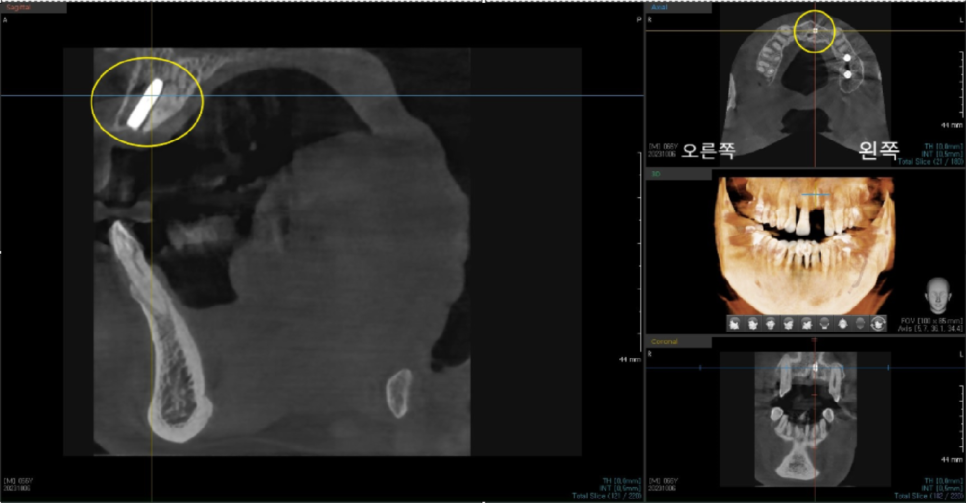

수술 이전에 3차원 CT 데이터와 3차원 구강 스캔 데이터를 가지고

모의 수술을 해본 후에 시뮬레이션 결과대로 식립할 수 있게

가이드를 맞춤 제작합니다.

저희 바르디 치과에서는

임플란트 수술 후에도 3D CT를 촬영하여

임플란트 식립 위치가 올바르게 되었는지

확인해 드립니다.